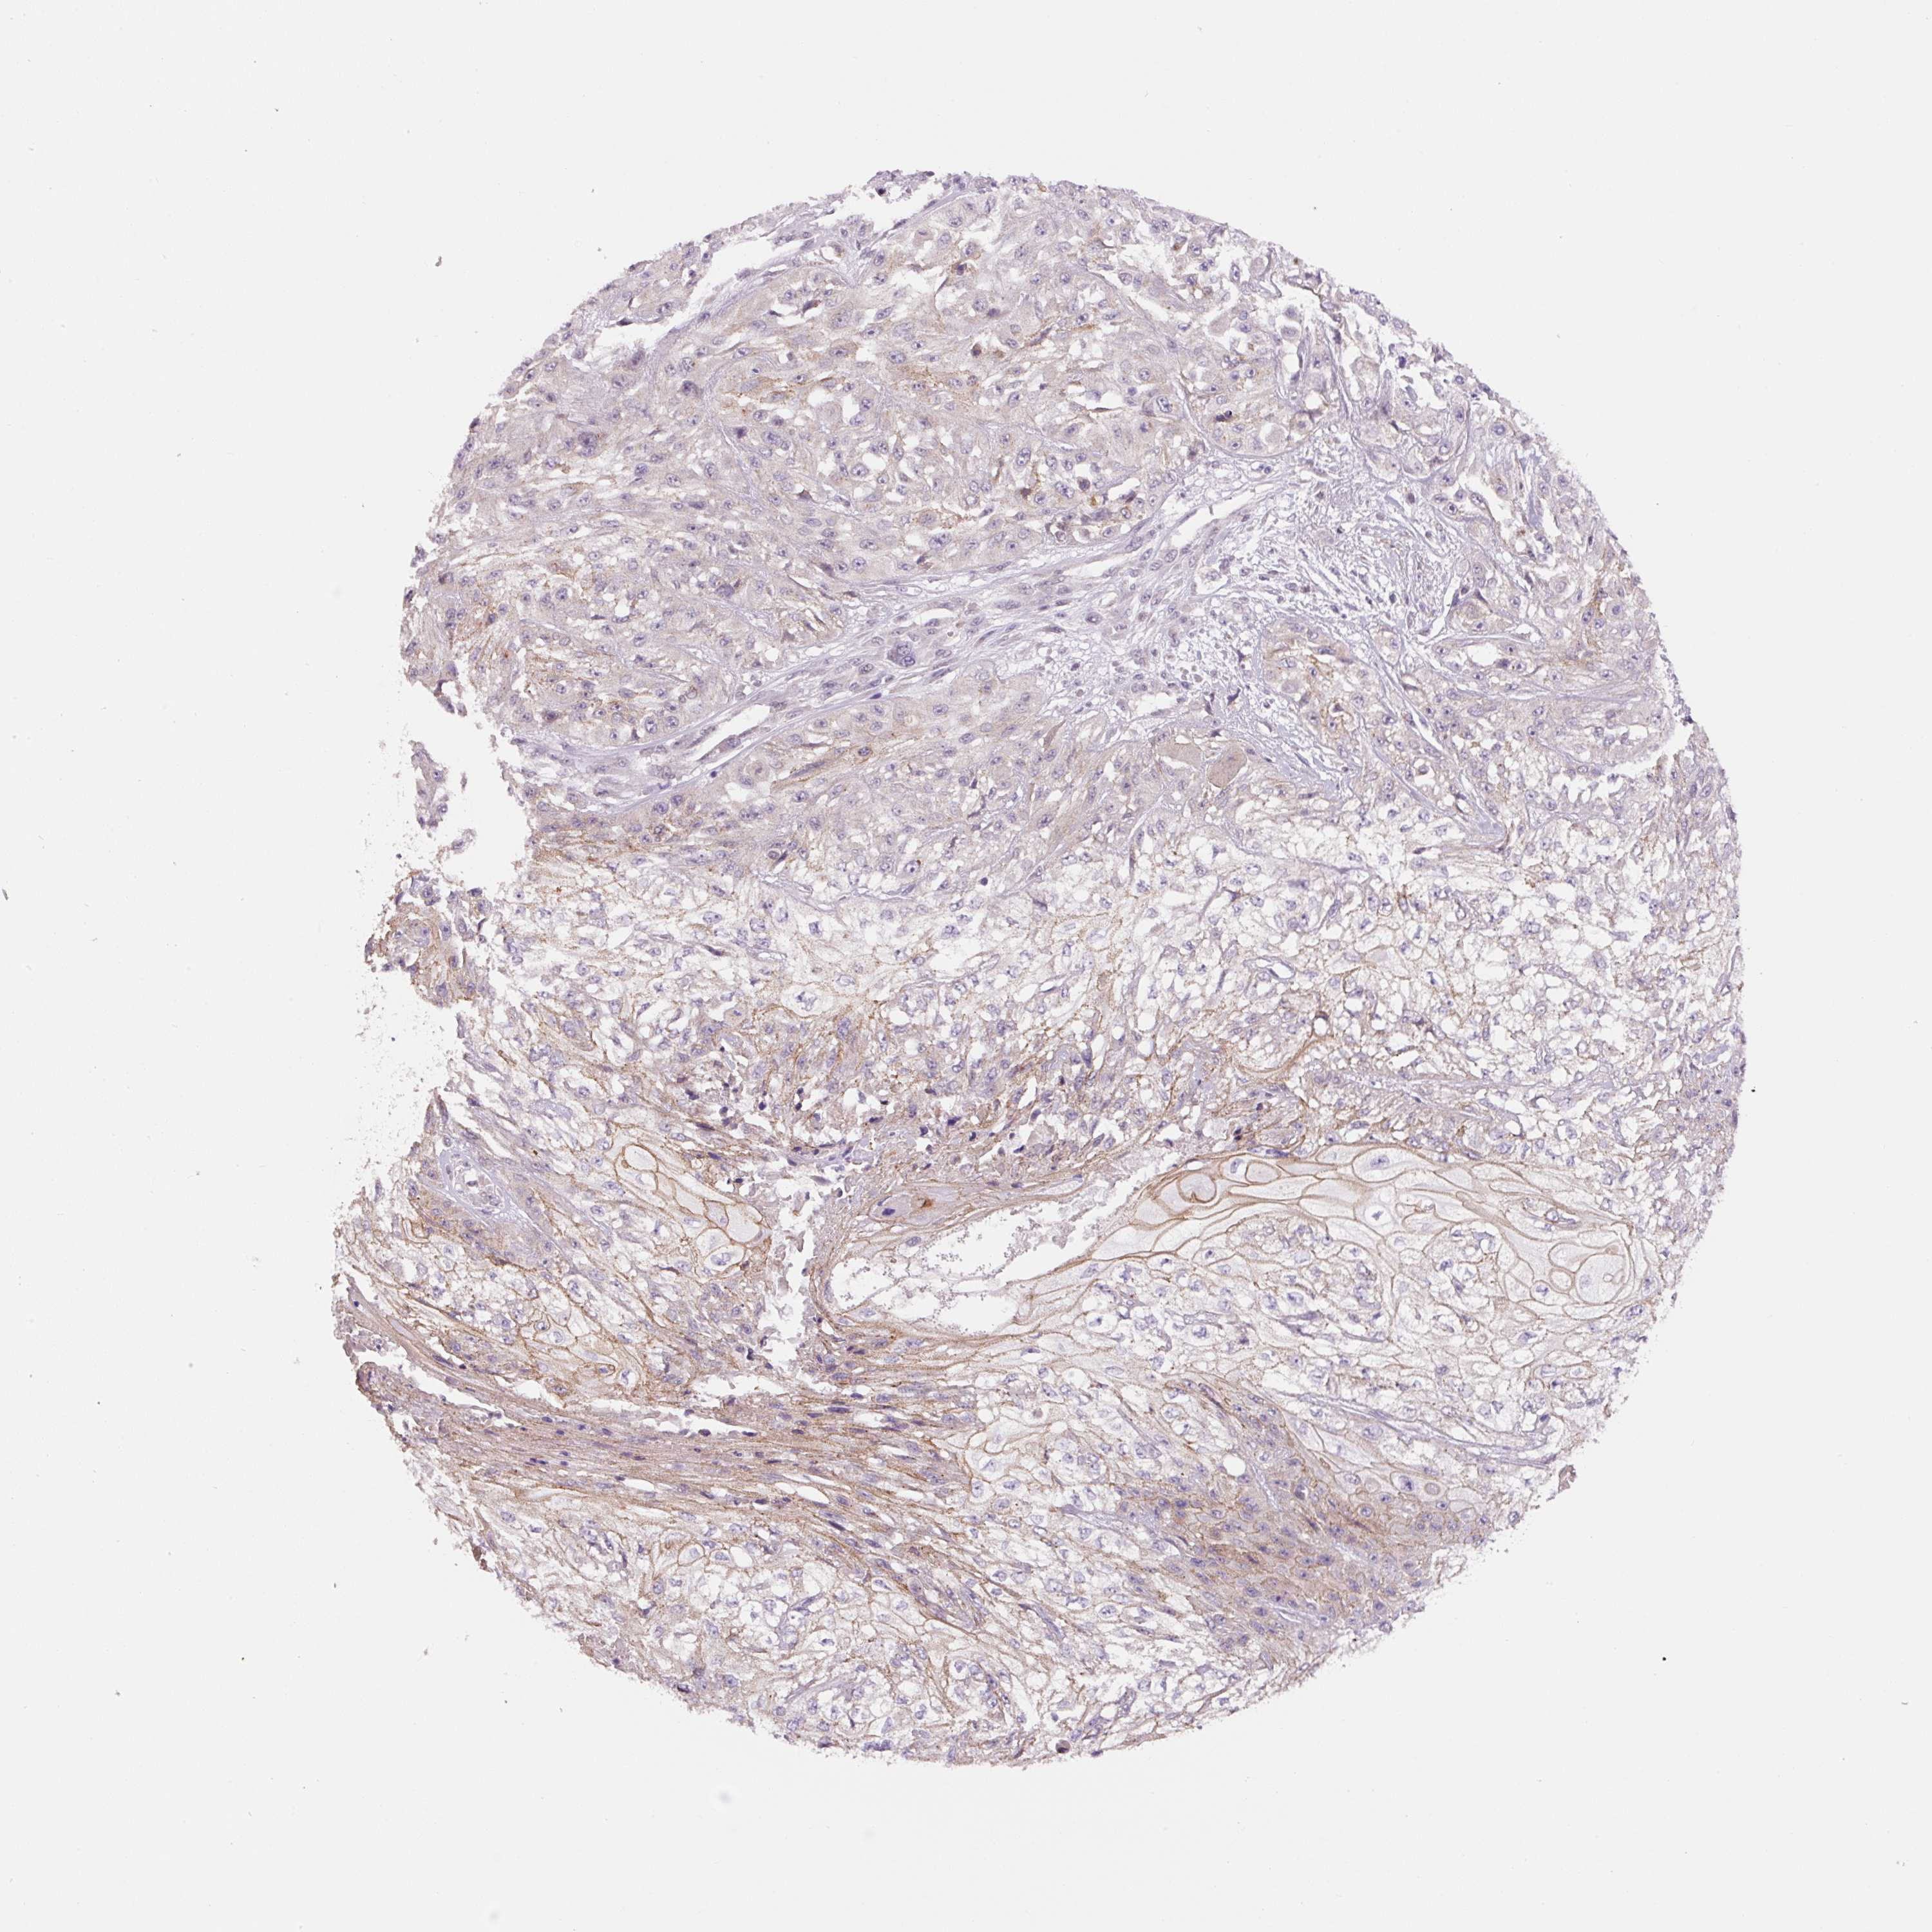

SKIN CANCER - Protein expressioni

A mouse-over function shows sample information and annotation data. Click on an image to view it in a full screen mode. Samples can be filtered based on level of antibody staining by selecting one or several of the following categories: high, medium, low and not detected. The assay and annotation is described here.

Each image is clickable and will lead to virtual microscopy that enables deeper exploration of all samples and also displays staining intensity scores, fraction scores and subcellular localization as well as patient and tissue information for each sample.

Antibody HPA051162

Staining

High

Medium

Low

Not detected

Intensity

Strong

Moderate

Weak

Negative

Quantity

>75%

75%-25%

<25%

None

Location

Nuclear

Cytoplasmic/membranous

Cytoplasmic/membranous,nuclear

Basal cell carcinoma